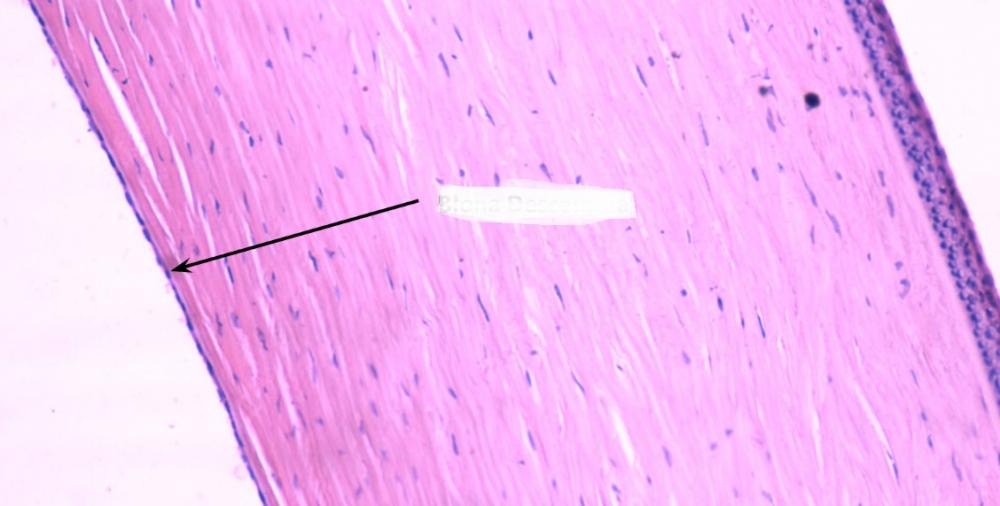

Pytanie 41

nabłonek jednowarstwowy płaski - błona Descemeta - (rogówka)